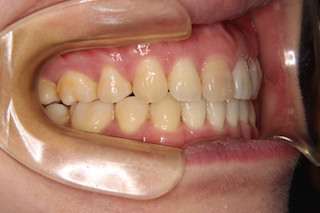

側面・・奥歯の噛み合わせは悪くありませんが、上下とも前歯が飛び出しているので前歯では噛み合いません

側面・・前後とも噛み合わせが決まりました!